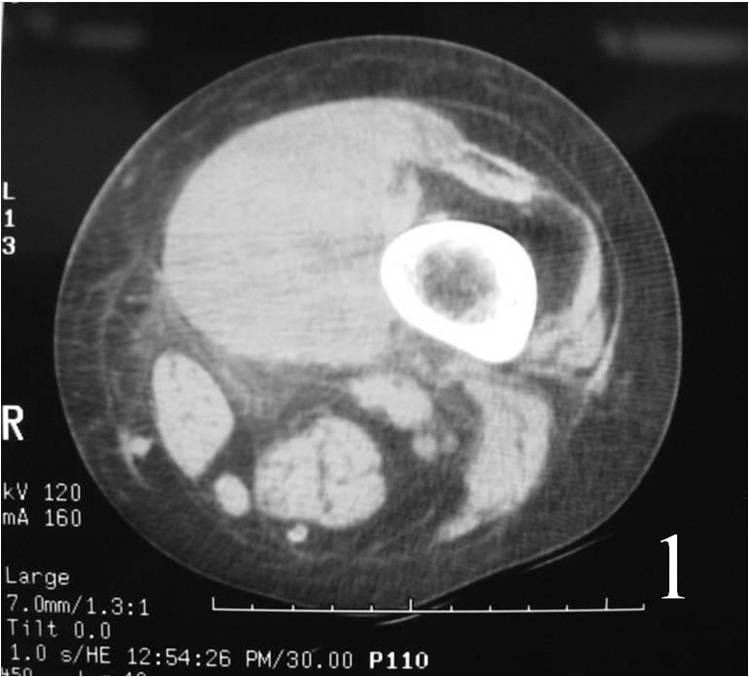

CT

Nonspecific mass (Fig. 1)

Frequently demonstrate areas of low attenuation,—>heterogeneous areas (hemorrhage, necrosis, or cystic change)